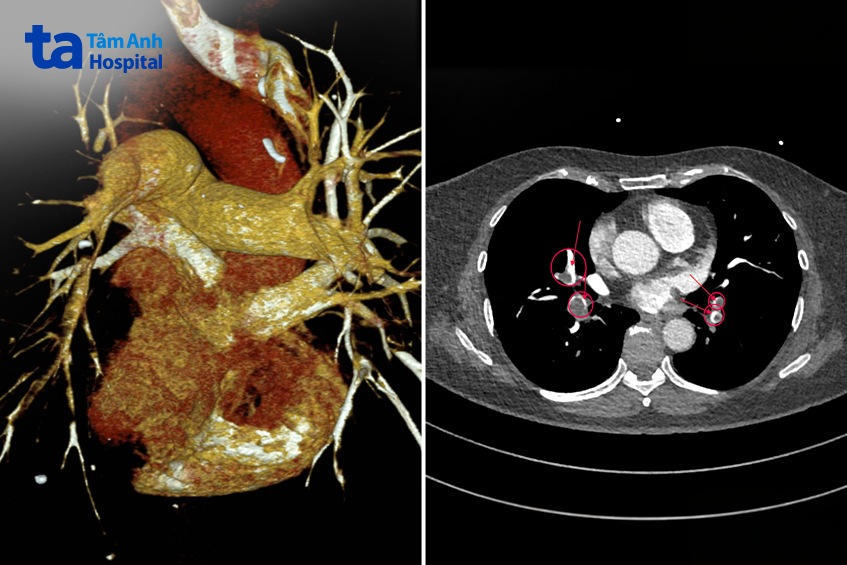

BS.CKI Phạm Đức Long, khoa Cấp cứu, chỉ định thực hiện các xét nghiệm, phát hiện chỉ số D-dimer tăng cao đến 8,87 µg/mL, tức vượt 18 lần ngưỡng bình thường (< 0,5 µg/mL) và triệu chứng lâm sàng nghi ngờ thuyên tắc phổi nhưng không loại trừ hội chứng động mạch vành cấp. Kết quả chụp cắt lớp vi tính theo kỹ thuật Triple Rule Out (đánh giá đồng thời động mạch vành, động mạch chủ và động mạch phổi) ghi nhận hệ động mạch vành không có tổn thương xơ vữa gây hẹp, động mạch chủ ngực không có dấu hiệu bóc tách. Tuy nhiên, hình ảnh CT phát hiện huyết khối ở hai nhánh chính động mạch phổi và các phân nhánh, trong đó có những vùng tắc bán phần, thậm chí gần như hoàn toàn.